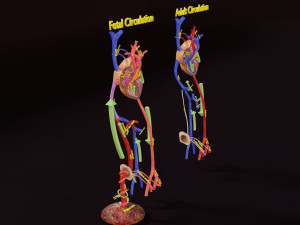

The model meshes include adult circulation versus circulation in Tetralogy of Fallot (TAF), arrow labels and text labels. The blood flow in a patient with Tetralogy of Fallot is outlined in this model. To contrast it to normal blood circulation a separate model of normal circulation is included. The Tetralogy of Fallot (OVER RIDING OF AORTA, PUL STENOSIS, VENTRICULAR SEPTAL DEFECT, RIGHT VENTRICULAR HYPERTROPHY), fossa, ligament teres , venosus, and arteriosus are duly depicted with proper labelling and blood flow directional arrows. Excellent model for teaching, demonstration and knowlegde of human body. The models include both procedural and image textures blend files separately. The texture file include diffuse, roughness and normal png and jpeg based on non overlapping UV maps.

डाउनलोड करें TAF Tetralogy of Fallot vs Normal circulation 3D मॉडल glb obj ply stl blend blend png 3mf fbx glb glb usd glb से deepuparmar777

tetralogy fallot pulmonary stenosis hypertrophy ventricular septal defect congenital heart disease human anatomy medical science cardiovascular blood flow cyanosis systemइस आइटम के लिए कोई कमेंट्स नहीं है।